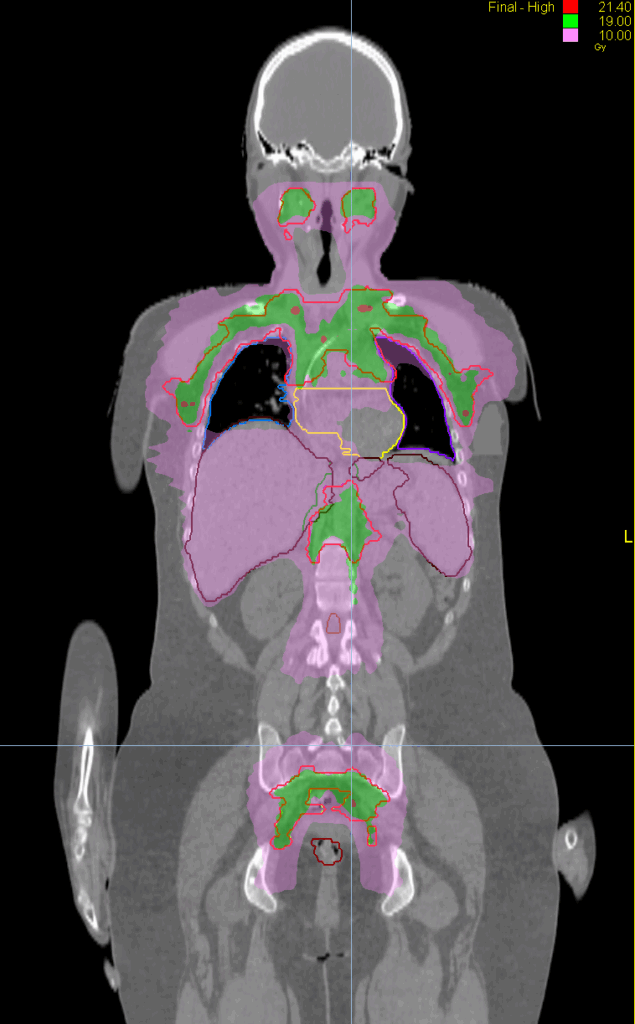

Treatment Plan Images

Fractionation / Protocol Used

20 Gy in 10 fractions

PTV(s) Volume, Length

5000 cc, 71 cm